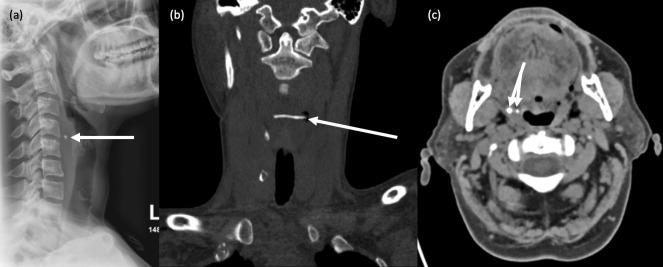

咽病理学的影像学表现。

Imaging of pharyngeal pathology.

The pharynx plays a significant role in swallowing and speech, and this is reflected in both its complex anatomy and degree of physiological motility. Patients who present with pharynx-related symptoms such as sore throat, globus, dysphagia or dysphonia will usually undergo visual and nasal endoscopic examination in the first instance. Imaging is frequently required to supplement clinical assessment and this typically involves MRI and CT. However, fluoroscopy, ultrasound and radionuclide imaging are valuable in certain clinical situations. The aforementioned complexity of the pharynx and the myriad of pathologies which may arise within it often make radiological evaluation challenging. In this pictorial review, we aim to provide a brief overview of cross-sectional pharyngeal anatomy and present the radiological features of a variety of pharyngeal pathologies, both benign and malignant.

咽在吞咽和言语中起着重要作用,这反映在其复杂的解剖结构和生理运动程度上。出现咽痛、咽部异物感、吞咽困难或发音困难等咽部相关症状的患者通常首先进行视诊和鼻内镜检查。影像学检查常需要补充临床评估,通常包括 MRI 和 CT。然而,透视、超声和放射性核素成像在某些临床情况下具有重要价值。上述咽的复杂性和可能发生的多种病理改变常常使影像学评估具有挑战性。在本影像学综述中,我们旨在简要概述咽的横断解剖结构,并介绍各种良性和恶性咽病变的影像学特征。